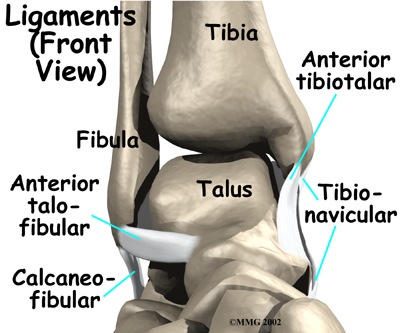

Ligaments are tough bands of tissue that help connect bones together. make up the lateral ligament complex on the side of the ankle farthest from the other ankle. They are the anterior talofibular ligament (ATFL), the calcaneofibular ligament (CFL), and the posterior talofibular ligament (PTFL). The common inversion injury to the ankle usually involves , the ATFL and CFL. Normally, the ATFL keeps the ankle from sliding forward, and the CFL keeps the ankle from rolling inward on its side.